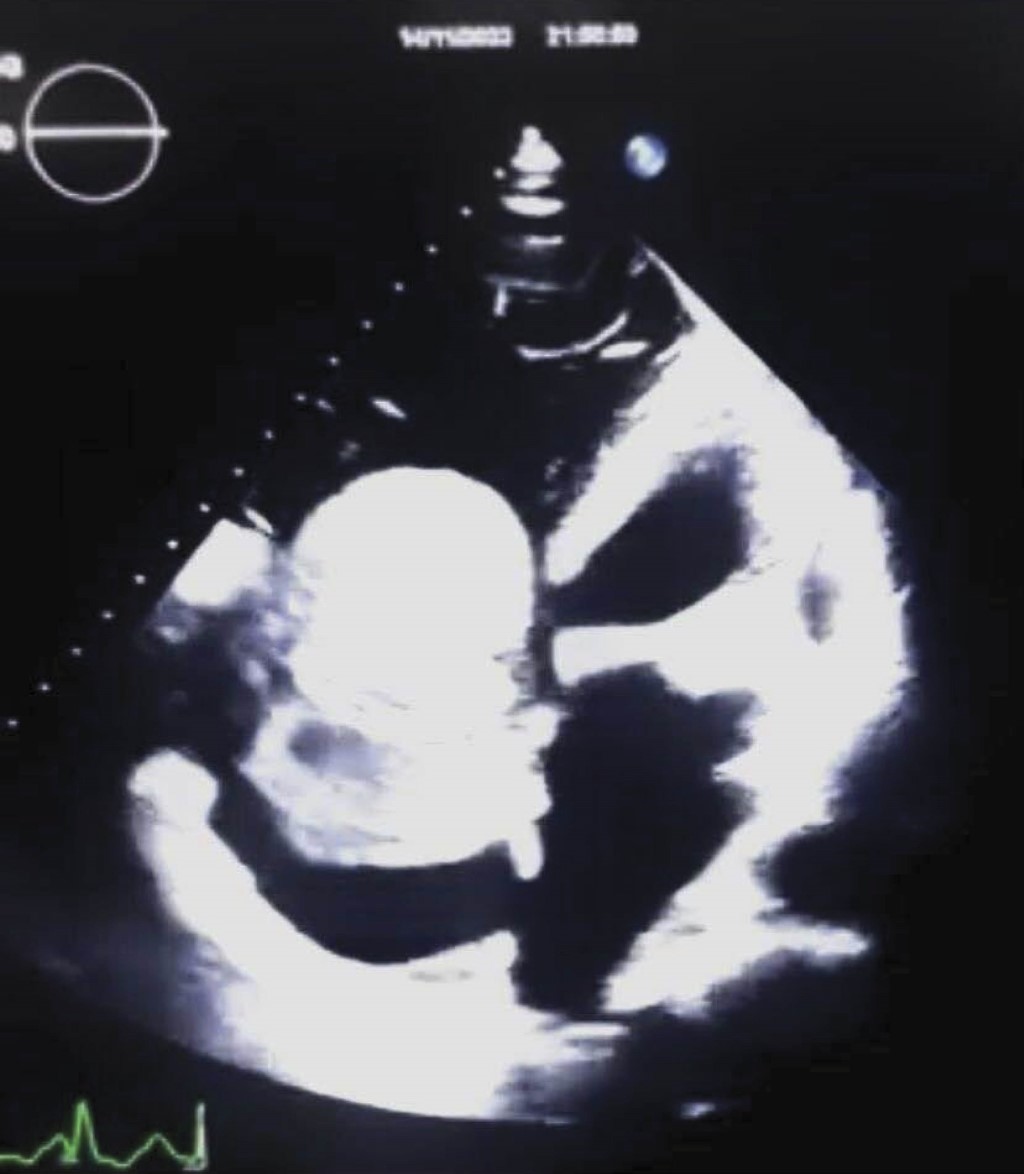

Introducción: los tumores cardíacos primarios son entidades raras cuya incidencia varía significativamente entre centros hospitalarios. Con el avance de técnicas diagnósticas, como la ecocardiografía y la cirugía con circulación extracorpórea, su manejo ha mejorado notablemente. Este estudio tuvo como objetivo determinar la incidencia y características clínicas de los tumores cardíacos en el Hospital General de México "Dr. Eduardo Liceaga" durante el período 2024–2025. Material: se realizó un estudio de cohorte prospectivo, descriptivo y transversal entre marzo de 2024 y marzo de 2025. Se incluyeron 11 pacientes mayores de 18 años con diagnóstico confirmado de tumor cardíaco. Resultados: se documentó una incidencia del 4.21% en relación con el total de cirugías realizadas (261). La mayoría de los pacientes fueron mujeres (63.64%) con una edad promedio de 56 años. Todos los tumores fueron primarios, siendo el 90.9% benignos (mixomas) y 9.09% malignos (sarcoma). La aurícula izquierda fue la localización más común (72.72%). Todos los pacientes fueron operados mediante esternotomía media, con un promedio de tiempo quirúrgico de 195 minutos. Dos pacientes (18.18%) requirieron reintervención por sangrado. No se registró mortalidad a los 30 días postoperatorios. La estancia hospitalaria promedio fue de 9.27 días. Conclusión: el mixoma auricular es el tumor cardíaco más frecuente, especialmente en mujeres de edad media, con predominancia en la aurícula izquierda. La cirugía continúa siendo el tratamiento de elección con baja tasa de complicaciones y buenos resultados a corto plazo. Es fundamental continuar con estudios multicéntricos para fortalecer el conocimiento epidemiológico de estas neoplasias.

Figura 1

Figura 2

Figura 3